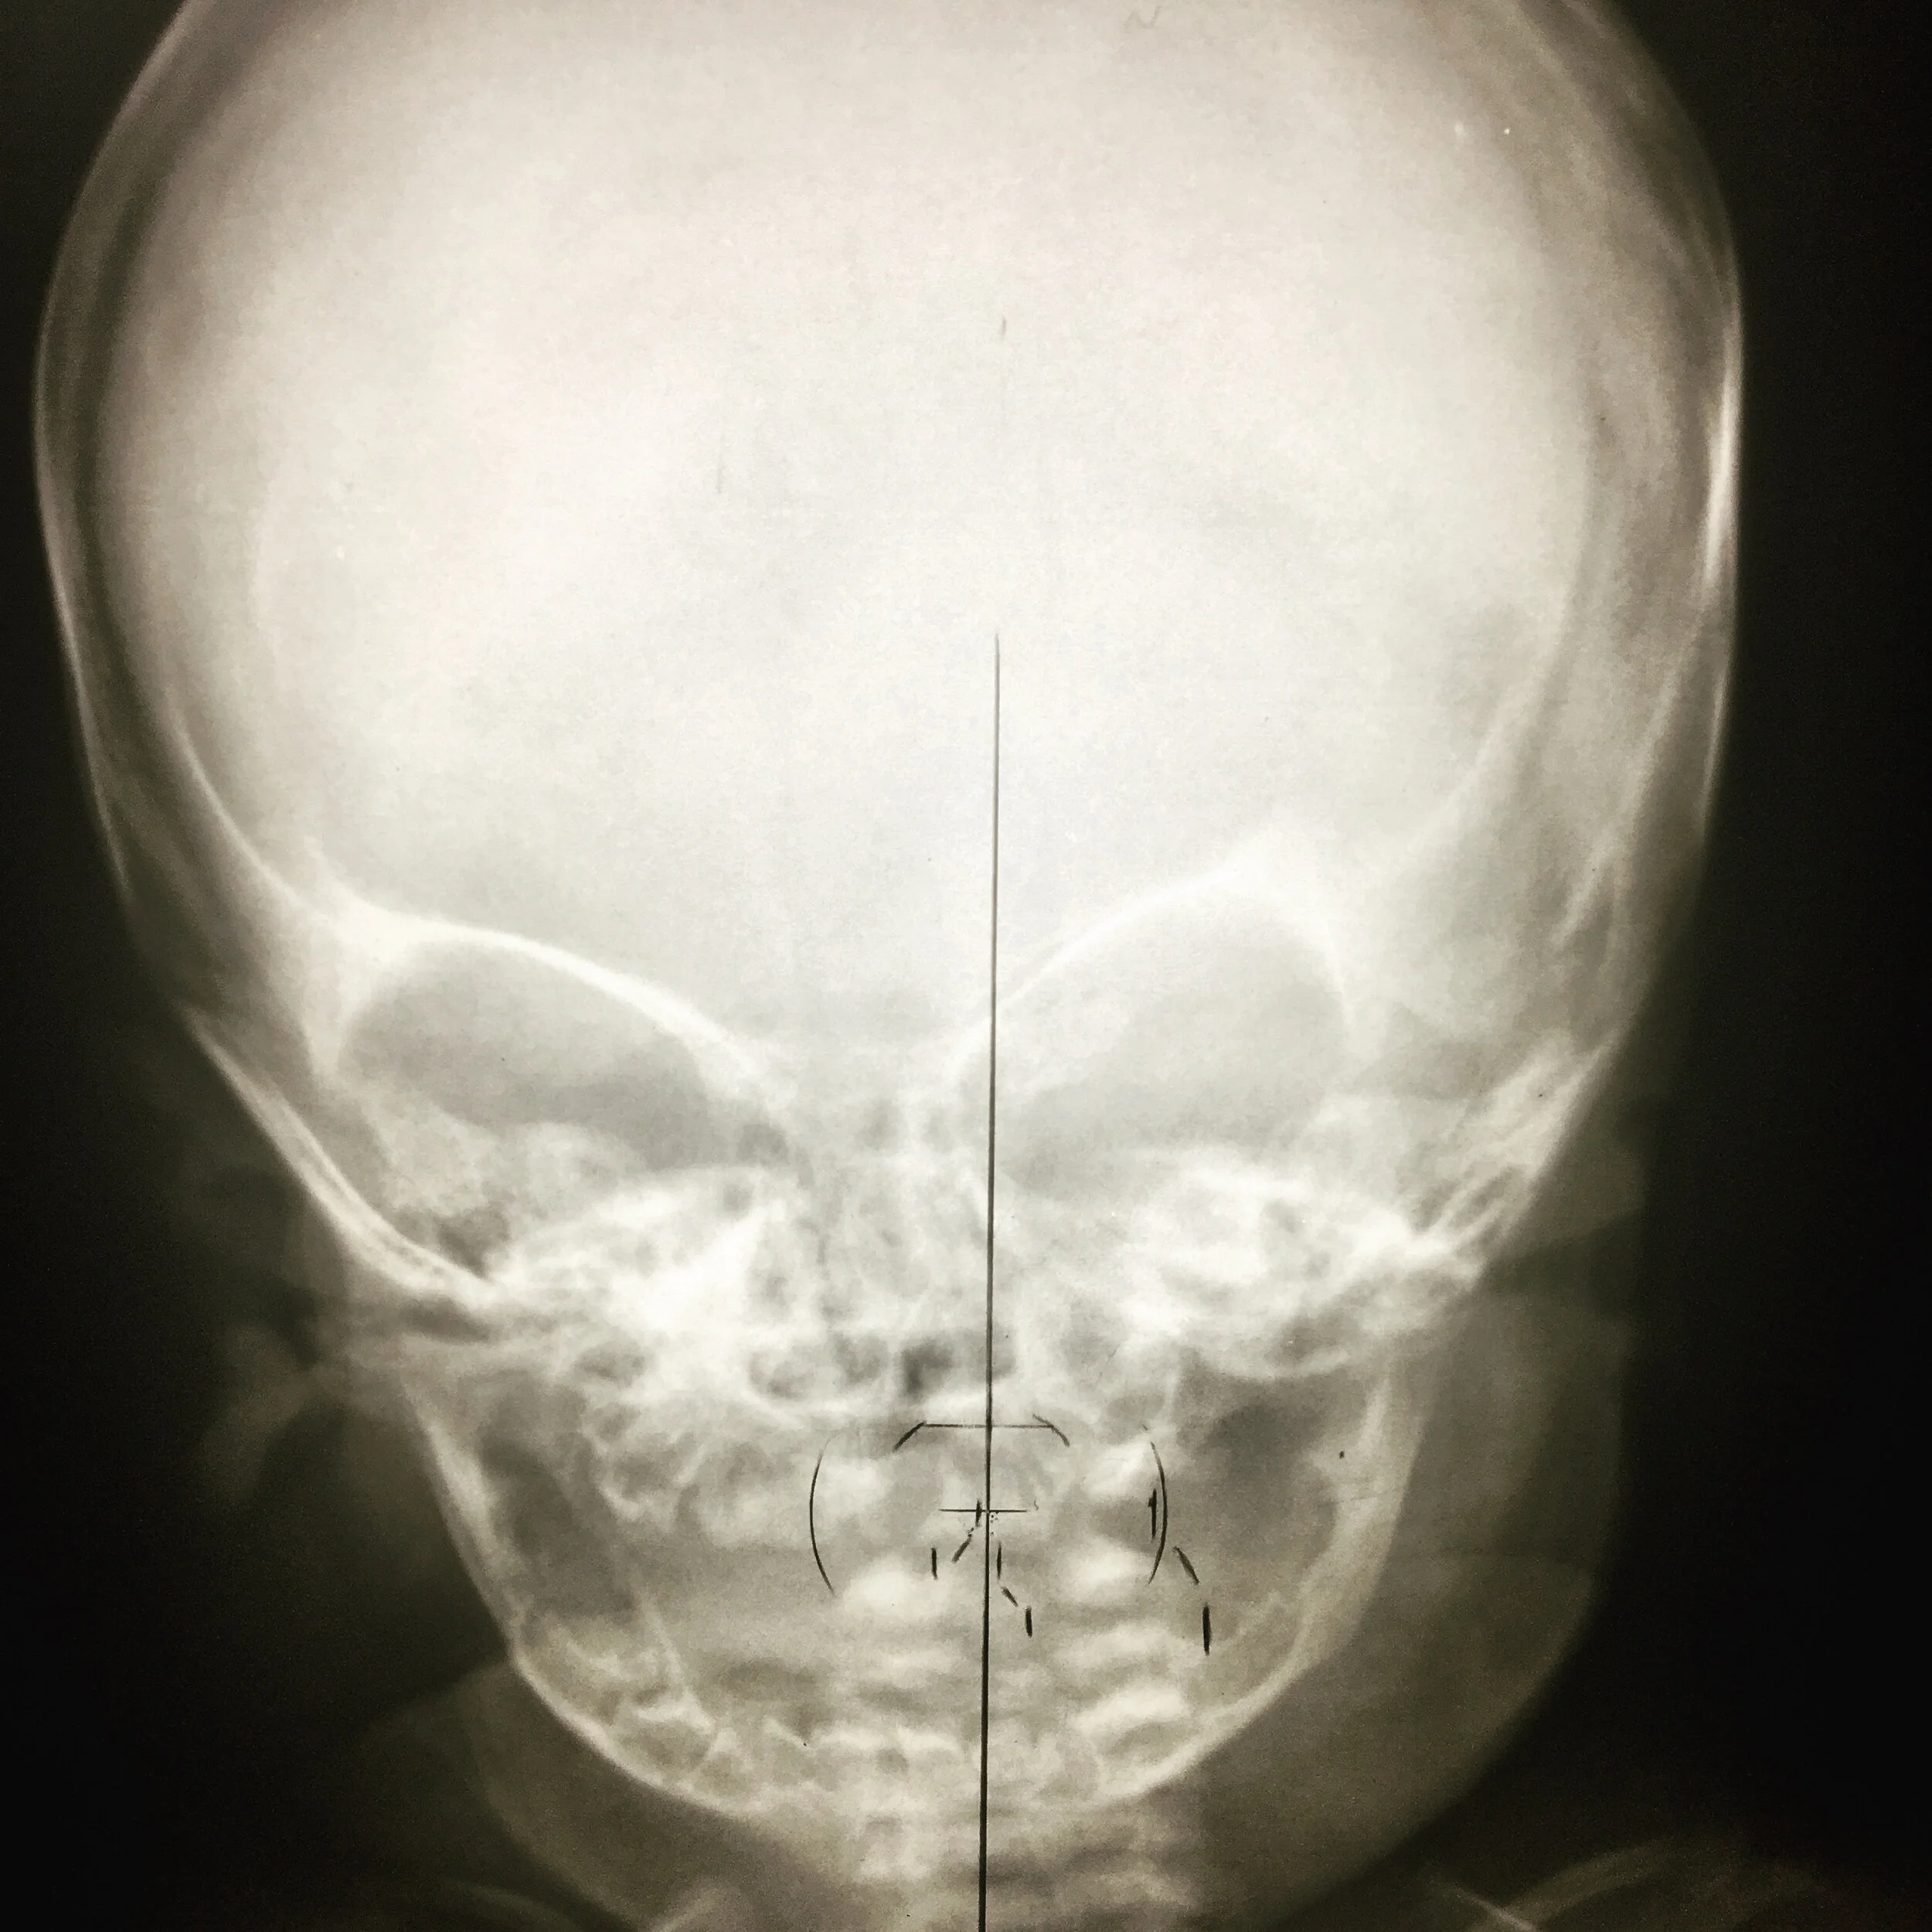

100+ Years of Pediatric Spinography

Chiropractors for over 100 years have trained to take and analyze X-Ray films.